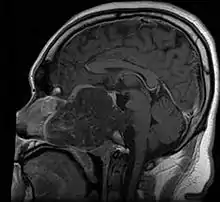

Anatomy

- In adults, remnants of notochord are present as the nucleus pulposus of the intravertebral discs, and distribution of tumors matches distribution of the remnants

- ~35% in sphenooccipital region (almost always involving clivus)

- 15-30% in vertebral column

- 30-50% in sacrococcygeal region